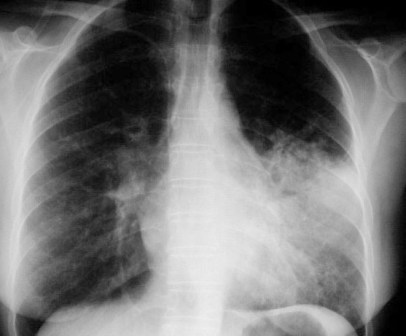

SIGNO DE LAS ALAS DE MARIPOSA

Signo de condensación alveolar bilateral en la radiografía posteroanterior (o anteroposterior) de tórax, propio del edema de pulmón de cualquier causa, aunque también puede verse en neumonías por gérmenes no habituales y hemorragia pulmonar. El signo recibe este nombre por la disposición perihiliar y simétrica de los infiltrados, que respetan la periferia pulmonar.

También se denomina signo de las alas de murciélago, pero está más extendido el término «alas de mariposa», que es, además, más gráfico.

La radiografía de este paciente con edema agudo de pulmón, muestra además, un tubo endotraqueal y un catéter de Swan-Ganz para medir las presiones de la arteria pulmonar.